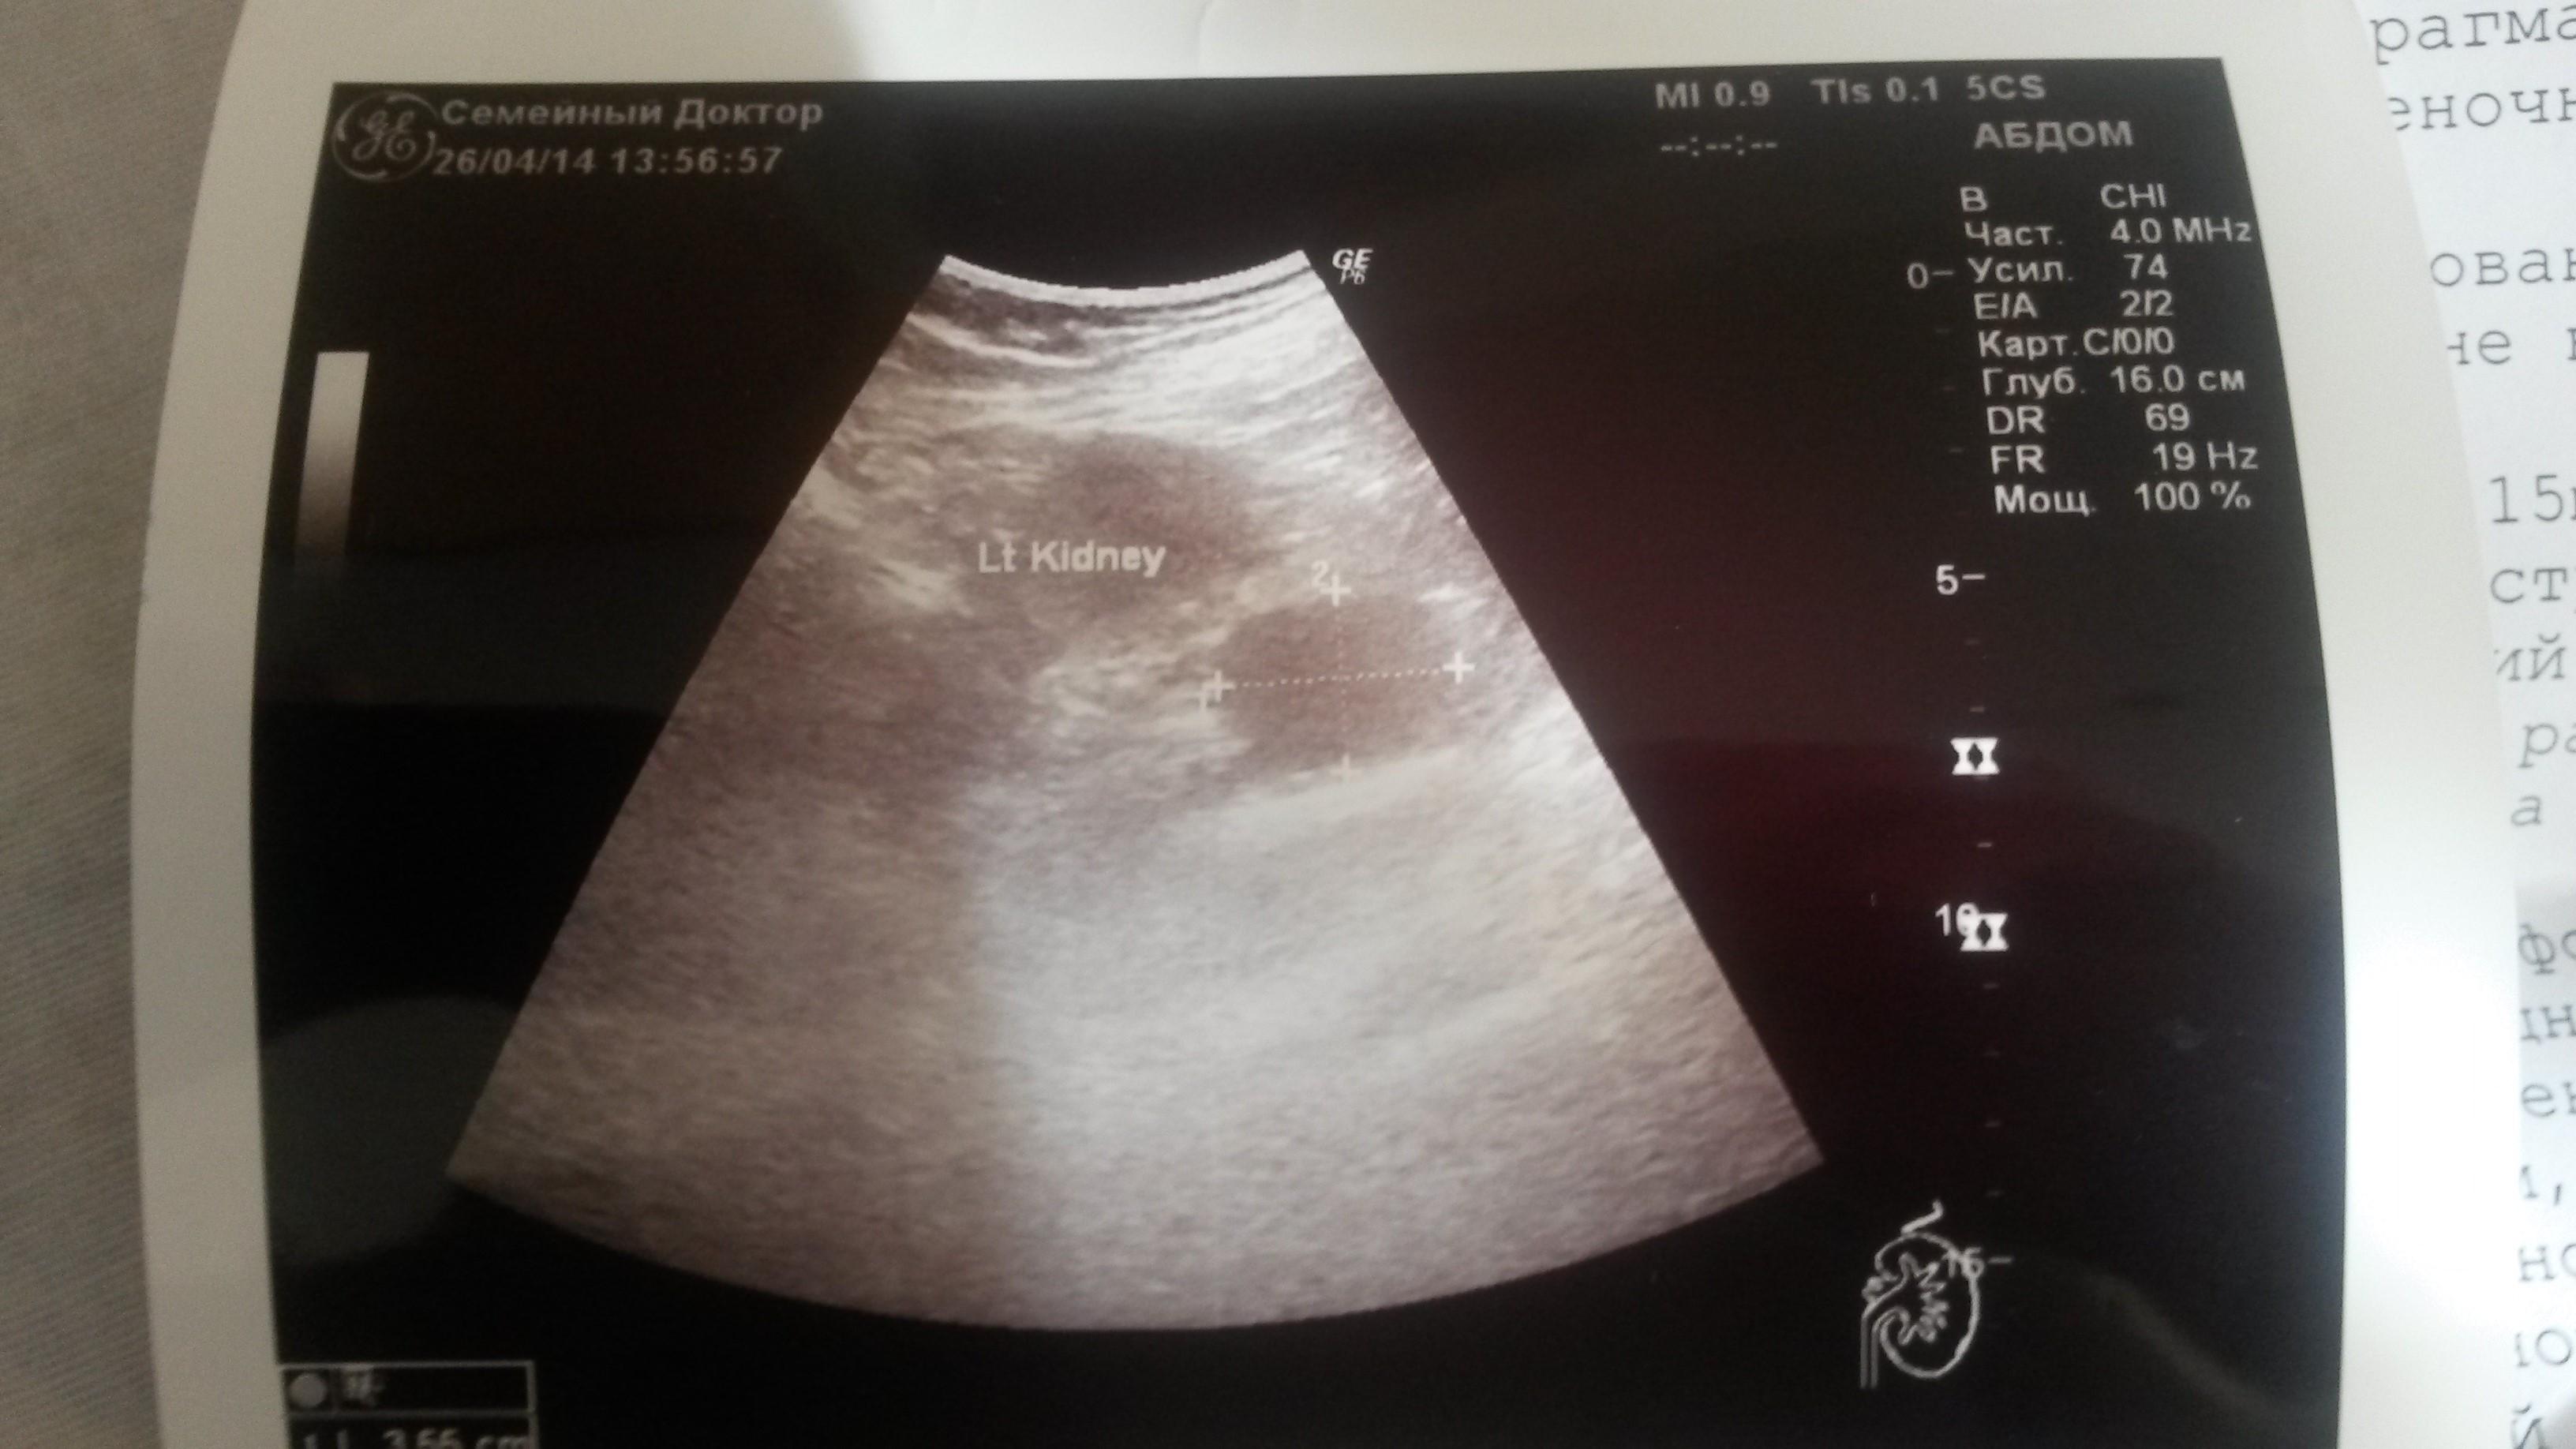

Здравствуйте, Мне 64 года на УЗИ брюшной полости в проекции левого надпочечника обнаружено гипоэхогенное образование 38 на 30 мм с четкими ровными контурами, однородной структуры. При ЦДК слабый смешанный кровоток. Размеры левой почки 120 на 58, контуры четкие, ровные, эхоструктура паренхимы однородная- 17 мм, ЧЛС центрально расположена. Сделали КТ...результаты Надпочечники расположены обычно. Отмечается утолщение тела и медиальной ножки левого надпочечника до 5 мм. В области надпочечником патологических образований не визуализируется. В заключении признаки гиперплазии левого надпочечника. На УЗИ есть объемное образование, а на КТ получается нет? Или может мы не правильно поняли результаты? Заранее спасибо.